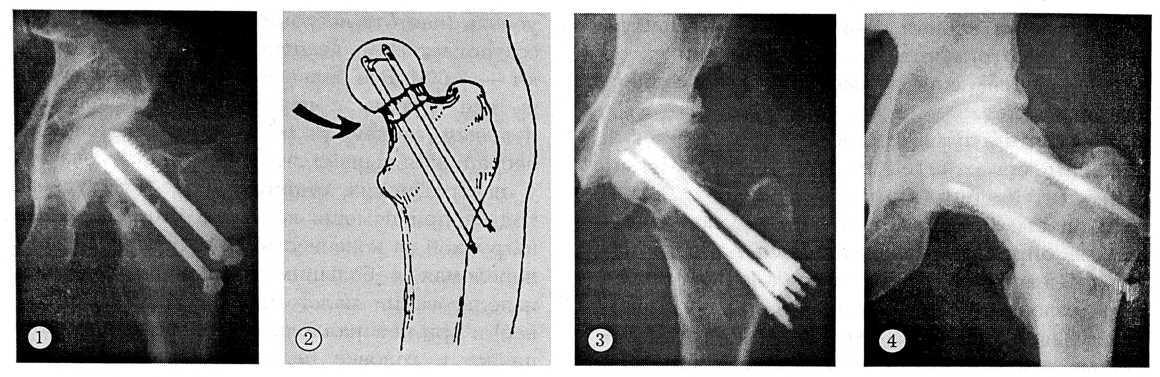

Широко применяется как в нашей стране, так и за рубежом мультиостеосинтез шейки бедра винтами DHS с осевым каналом и резьбой для губчатой кости. По направляющей спице через небольшие разрезы вводятся, как правило, 3 винта — по нижнему, верхнему контурам шейки и через центр головки (рис. 1). Создается прочный компрессионный остеосинтез, позволяющий больному в относительно ранние сроки (4—6 нед) передвигаться при помощи костылей с нагрузкой на конечность [8]. Частота несращения и асептического некроза головки бедра приблизительно такая же, как и при мультиостеосинтезе гвоздями Knowles.

В 1975 г. Hansson предложил оригинальный фиксатор для оперативного лечения детей с эпифизеолизом головки бедренной кости. Для мультиостеосинтеза переломов шейки бедра это устройство стало использоваться с 1980 г. Оно представляет собой анкерный фиксатор, имеющий трубчатое сечение с ребристой поверхностью диаметром 6,5 мм. Анкер в виде выступающего крючка выводится в проксимальном конце фиксатора на 10 мм и закрепляется в субхондральном слое головки, что обеспечивает достаточную прочность остеосинтеза и предотвращает миграцию как в центральном, так и в проксимальном направлении. Два фиксатора Hansson, расположенные строго параллельно, вводятся в шейку и головку бедра через костные каналы, образованные сверлом того же диаметра (рис. 2). Таким образом, во время операции отпадает необходимость во вколачивании или вращении фиксирующего устройства. «Гладкий профиль» фиксаторов Hansson и параллельное их расположение способствуют проявлению физиологической компрессии в зоне перелома, позволяют поддерживать постоянный контакт между отломками в течение периода неизбежной при сращении переломов шейки бедра резорбции с ее укорочением. При этом уменьшается риск несращения, миграции фиксаторов и оптимизируется процесс костной регенерации внутрисуставного перелома. По данным В. Stromqvist и соавт. [11, 12], при использовании фиксатора Hansson несращение переломов шейки бедренной кости наблюдалось у 12% больных, асептический некроз головки — у 5%. В отдаленные сроки неудовлетворительные исходы составили 23%.

Рис. 1. Остеосинтез шейки бедра тремя компрессирующими винтами АО. 2. Схема остеосинтеза шейки бедра фиксаторами Hansson. 3. Остеосинтез шейки бедра фиксаторами Н.А. Шестерни. 4. Остеосинтез шейки бедра двумя субкортикальными винтами со сплошной резьбой.

В нашей стране в последние годы большой вклад в разработку теории и практики остеосинтеза шейки бедра, в том числе мультиостеосинтеза, внес Н.А. Шестерня [2]. Им предложен малотравматичный перкутанный остеосинтез четырьмя цилиндрическими стержнями, имеющими две разношаговые резьбы, причем одна из них размещена на основании упорного конуса. Каждый стержень снабжен хвостовиком, который используется при установке фиксатора через кондукторную втулку в головку и шейку бедра. Фиксаторы вводятся таким образом, что проксимальные концы их конвергируют в головке бедра во фронтальной плоскости и дивергируют — в сагиттальной (рис. 3).

В течение последних 4 лет в нашей клинике успешно используется предложенный В.И. Зорей (патент РФ 2056802) парный субкортикальный остеосинтез шейки бедра. Фиксация отломков осуществляется двумя параллельно введенными винтами, сплошная резьбовая поверхность которых погружена в субкортикальный слой верхней и нижней стенок фрагментов шейки (рис. 4).